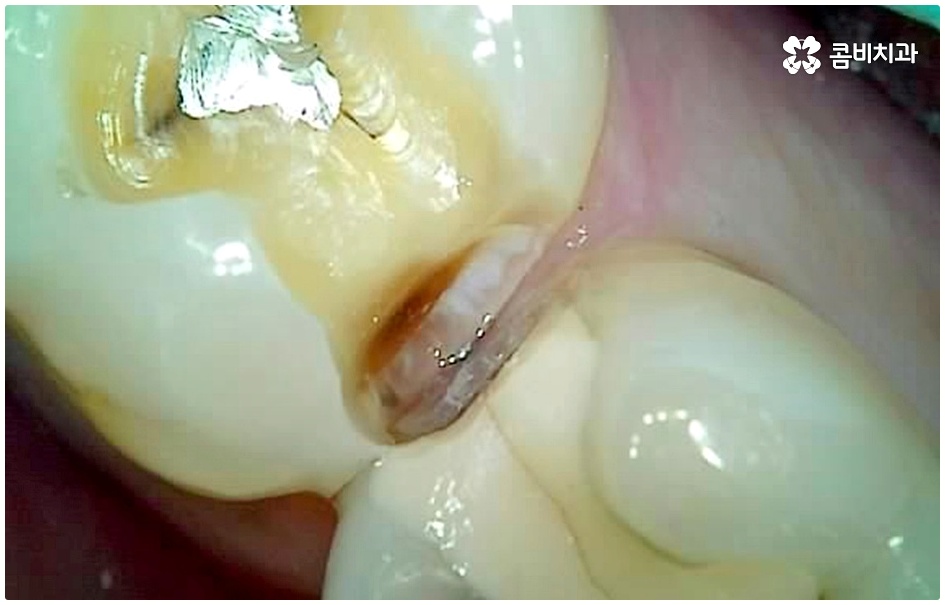

이 때 교합면, 즉 치아의 씹는 면이 아닌 치아 사이 충치가 생겼다면 쉽게 발견하기도 어렵고 치료를 위한 접근 역시 까다롭기 때문에 주의하실 필요가 있습니다. 물론 가장 흔하게 발생하는 것은 넓고 홈이 파여 있으며 직접 음식물을 저작하는 교합면에 생기는 충치일 것이나 음식물 찌꺼기가 끼기 쉽고 세균이 서식하기도 쉬우며 양치질을 하더라도 칫솔모가 잘 닿지 않기 때문에 관리가 어려운 치아 사이 좁은 틈새에도 역시 충치가 잘 생길 수 있는 거예요.

치아 사이 충치는 치아끼리 맞닿아 있는 부분이라 노출이 잘 되지 않기 때문에 육안으로 식별이 어려운 경우가 많은데, 만약 눈으로 확인될 정도라면 질환이 이미 많이 진행한 상태이므로 명동치과 에서 빠른 치료를 받아주실 필요가 있어요.

치아의 구조를 살펴보면 겉표면인 단단한 법랑질은 교합면에서 가장 두껍고 잇몸쪽으로 갈수록 얇아지기 때문에 치아 사이의 인접면은 치아의 신경과 한층 가까워서 충치가 조금만 진행되어도 신경치료를 받아야 할 수 있으며 인접면 충치가 심하여 레진이나 인레이 수복으로 치아의 외형을 재현하기 어려운 경우에는 치아 전체를 다듬어 씌우는 명동치과 크라운 치료를 해줘야 하니 부담이 커지기 전에 치료 시기를 놓치지 않도록 주의하시는 게 좋을 거예요.